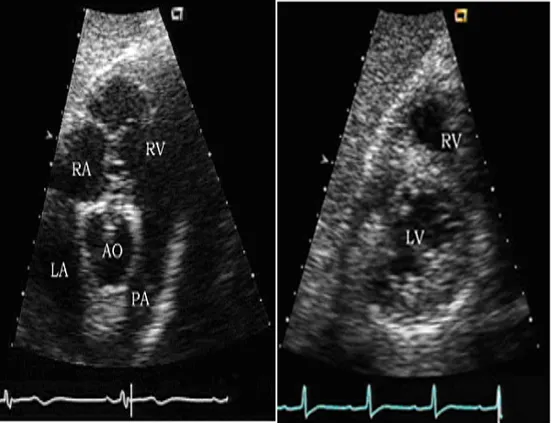

胸骨旁大动脉短轴切面

探头位置:探头置于胸骨左缘2、3肋间,在左心室长轴切面基础上探头顺钟向旋转90°或者是在大动脉短轴切面基础上心尖偏转法。

观察内容:

● 腔室大小:右室流出道、肺动脉。

● 瓣膜活动:主动脉瓣、肺动脉瓣。

● 结构的连续性:房间隔、室间隔、动脉导管。

心尖四腔心切面

探头位置:探头置于心尖搏动点处;探头指向右胸锁关节。

观察内容

● 瓣膜活动:二尖瓣及三尖瓣形态结构与活动。

● 腔室大小:左房,左室,右房,右室。

● 室壁运动:左室壁的侧壁和后室间隔。

● 室壁厚度:左室壁的侧壁和后室间隔。

● 结构的连续:房间隔和室间隔。

● Simpson心功能的测定。